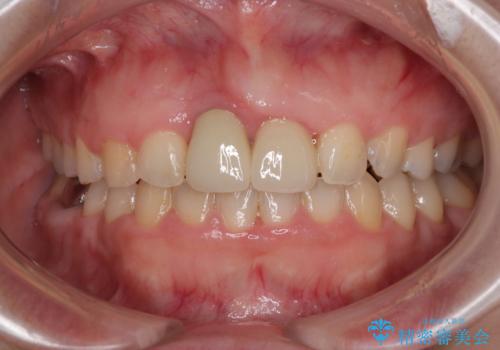

前歯のクラウンは変色が顕著なため、矯正治療後にオールセラミッククラウンによる補綴治療を行うこととしました。

前歯のクラウンは、歯肉内深くに削り込まれており、歯肉の炎症が継続していたため、矯正治療後に歯周外科処置を行い、歯肉の腫れを改善させました。